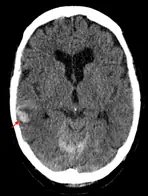

TC léger

Traumatisme cranien leger